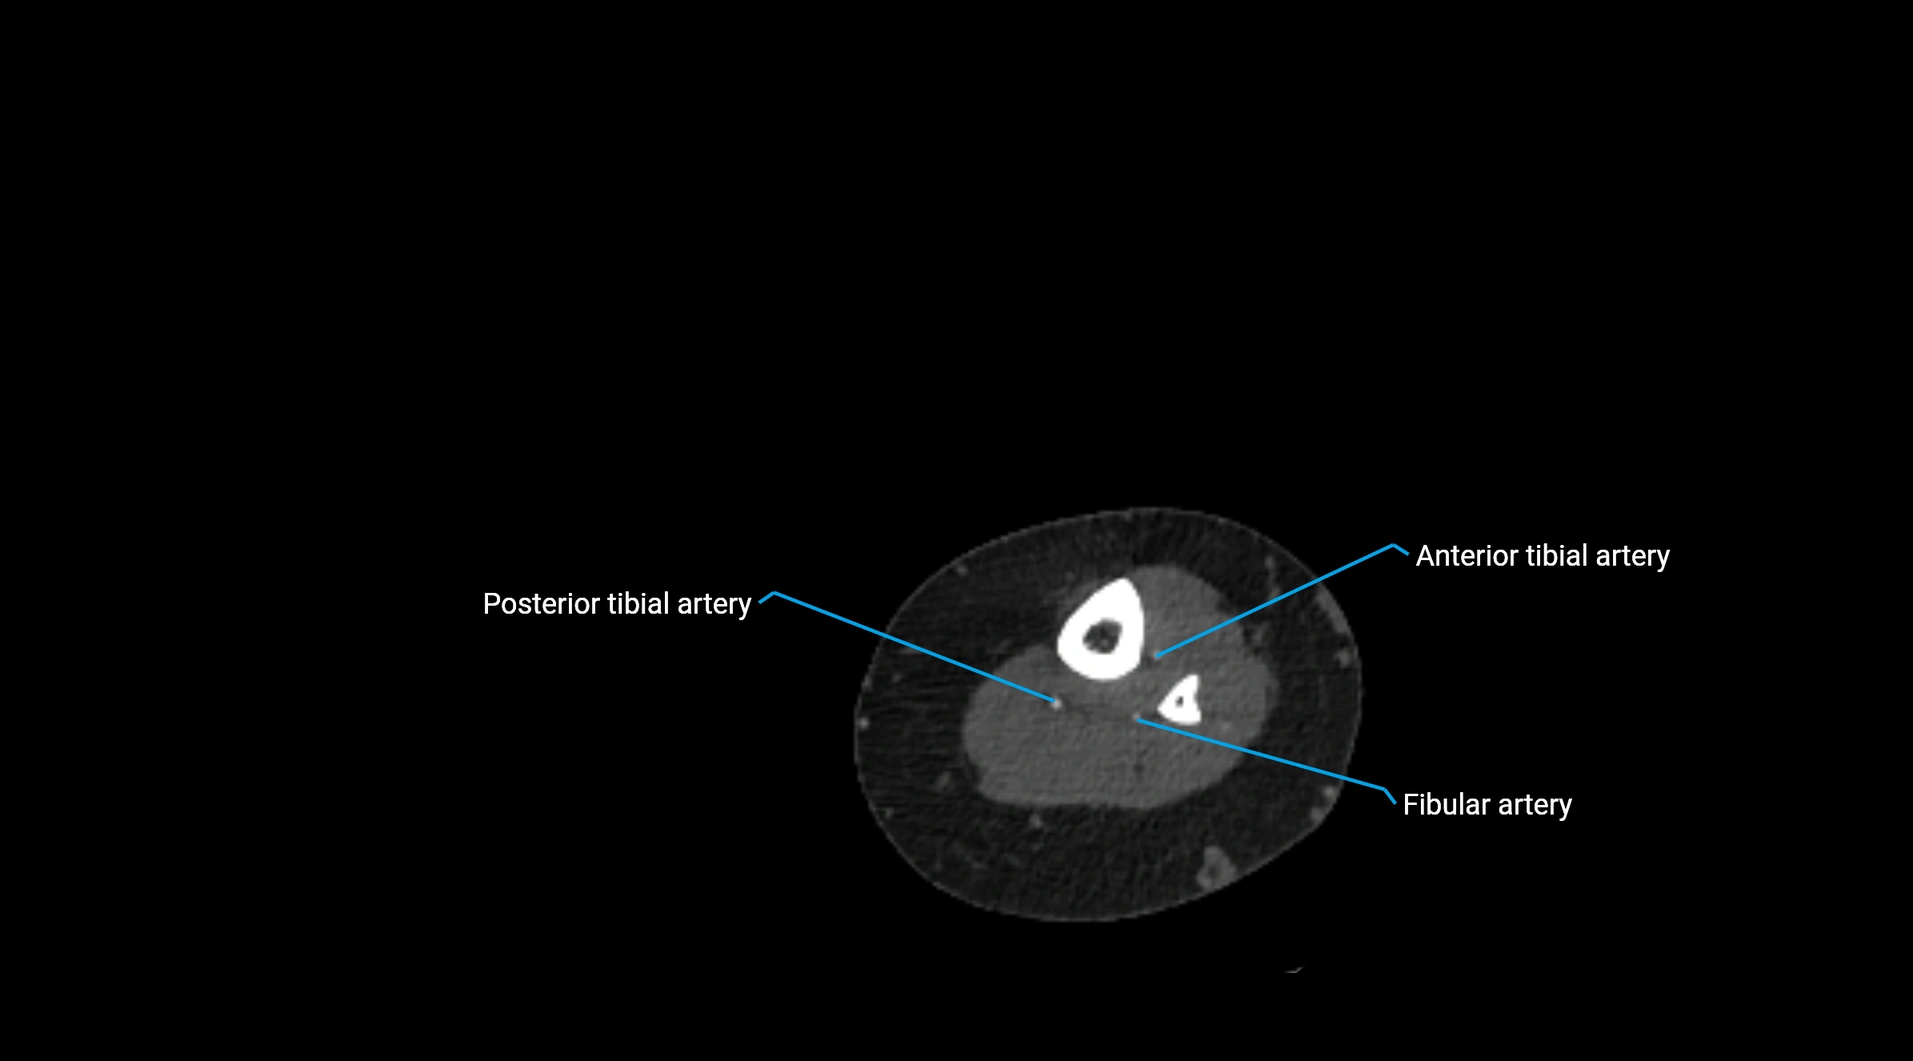

Contrast-enhanced CT (CTA):

• Gold standard for abdominal aortic imaging

• Provides excellent detail of lumen, wall, aneurysm, thrombus, and branch vessels

• Multiplanar and 3D reconstructions help in aneurysm measurement, stent graft planning, and dissection evaluation

• Detects acute rupture, traumatic injury, or occlusion with high sensitivity